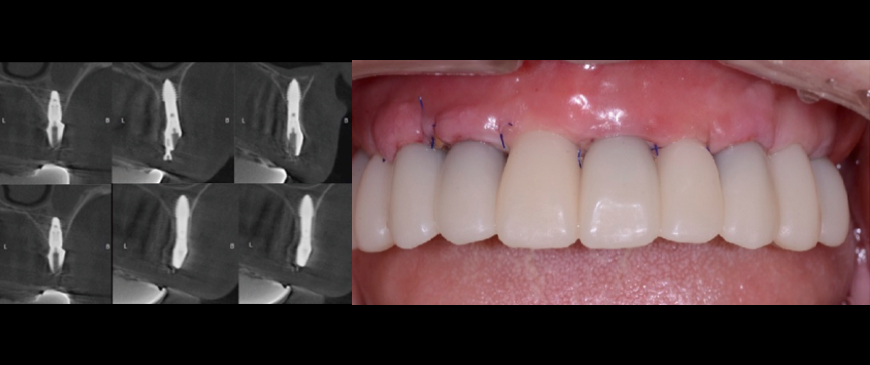

After approximately eight weeks, scanning was performed for impression-taking, followed by the placement of a customized abutment based on the BOPT (Biologically Oriented Preparation Technique) concept and a PMMA provisional bridge.

Fig 10

The provisional restoration was used for about three weeks, after which the final prosthesis was delivered.

Fig 11

Intraoral Clinical Images, Radiographs, and CBCT Scans at Three Months After Loading Although this represents a relatively short follow-up period, the clinical and radiographic evaluation at three months post-loading showed comparable outcomes to conventional Blue Diamond (BD) implant cases, demonstrating no signs of compromise in stability or bone response.